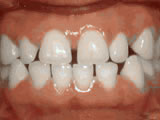

Overjet - Protruding front teeth

overjet beforeBefore

overjet afterAfter

At age ten, patient had a big overjet with the top teeth protruding beyond the bottom. She had two phases of treatment. The first helped her jaws to grow more harmoniously and the second aligned her teeth and bite. At age 13, she was proudly displaying her new smile.